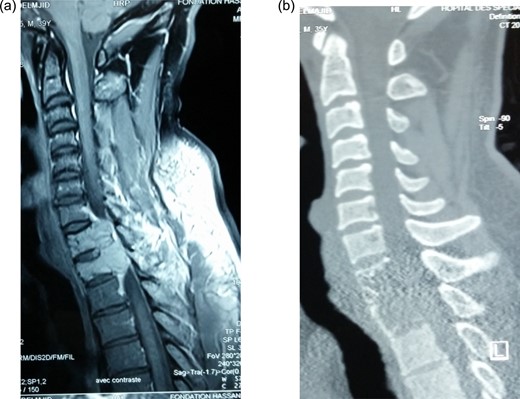

Postoperative sagittal CT showing (a) hook and rod stabilization posteriorly, and (b) bone graft and plate fixation anteriorly after corporectomy of D1 and D2.

Given this diagnosis, a second-stage surgery was performed 2 weeks later. This was performed by an anterior approach whereby cervicothoracic incision extending from lower cervical (C6) to upper thoracic (D3) was performed. It involved detachment of two heads of sternocleidomastoid muscles on the right side, and medial third of right clavicle was excised. The innominate artery and superior vena cava were identified and retracted exposing pathological vertebrae. Corpectomies of D1–D2 carried out, and residual tumor on posterior longitudinal ligament (PLL) and other surrounding structure was excised. Strut graft from the clavicle was placed to bridge the defect and stabilized by anterior plate bridging between C7 and D3.

He fared well postsurgery, at 4 weeks, the neurological deficit improved and the power was grade 4/5. At 6 weeks, he had fully recovery of sensorimotor functions on lower limbs and trunk. The control CT scan showed a good restoration of the spinal canal dimensions. At 3 months, the patient has no back pain. He did not receive radiation therapy as it has been found to be controversial interims of recurrence.